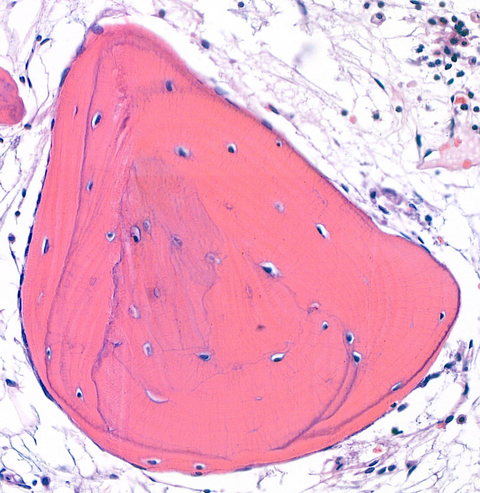

OsteoVision: AI to Decode Bone Healing

Developing AI methods to reveal patient-specific patterns in bone tissue organization and healing.